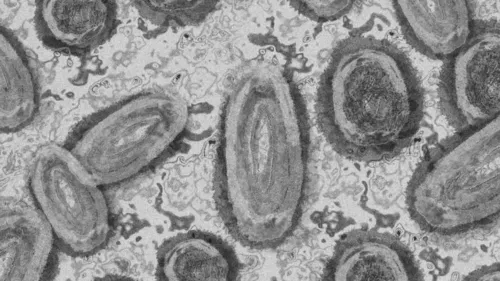

O Ministério da Saúde foi notificado sobre o oitavo caso registrado no Brasil do vírus monkeypox, conhecido como varíola dos macacos O paciente é um homem de 25 anos, morador de Maricá, no Rio de Janeiro. Ele não viajou para o exterior, mas teve contato com estrangeiros.

O caso foi confirmado pelo Laboratório de Enterovirus do Instituto Oswaldo Cruz, no Rio, que utilizou o método de Isolamento Viral para fazer o diagnóstico.

Conforme informações do Ministério da Saúde, o paciente está com quadro clínico estável, sem complicações e é monitorado pelo Instituto Nacional de Infectologia e pelas secretarias de Saúde do estado e do município.

“Todas as medidas de contenção e controle foram adotadas imediatamente após a comunicação de que se tratava de um caso suspeito de monkeypox, com o isolamento do paciente e rastreamento dos seus contatos”, informou o Ministério da Saúde, que notificou a Organização Mundial de Saúde (OMS) sobre o caso.

Dois oito casos confirmados no país até o momento, quatro foram em São Paulo, dois no Rio Grande do Sul e dois no Rio de Janeiro. Há, ainda, seis casos em investigação.

A varíola dos macacos era considerada endêmica em países da África Central e da África Ocidental, mas nos últimos meses houve relatos da doença em diversos outros países não endêmicos, especialmente na Europa, que já responde por 84% dos casos notificados, segundo a OMS.

Entre os dias 1º de janeiro e 15 de junho deste ano, a OMS foi notificada sobre 2.103 casos confirmados da varíola do macaco, em 42 países, assim como um caso provável e uma morte.